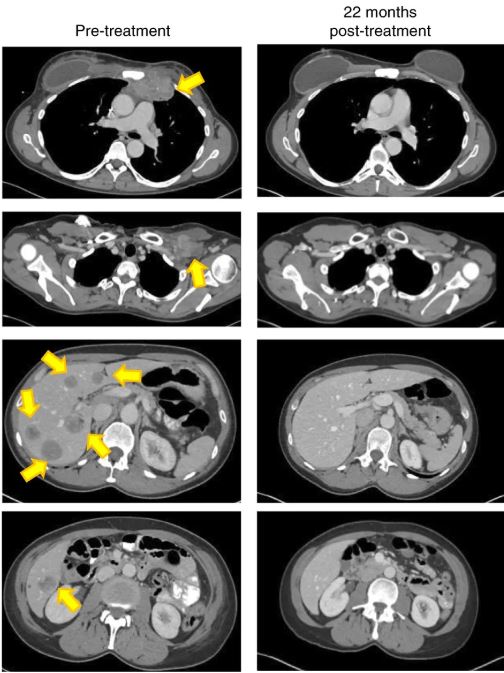

Предлагаю фрагмент рисунка 2d из оригинальной статьи. Даже впервые видящим томограмму будет очевидно, что все отмеченные желтыми стрелками посторонние включения исчезли.

Охренеть, да. Фантастика.

Да ну, большинство народу здесь просто набор пятен увидят. Лучше вот эту, где графики объема всего в ноль уходят.